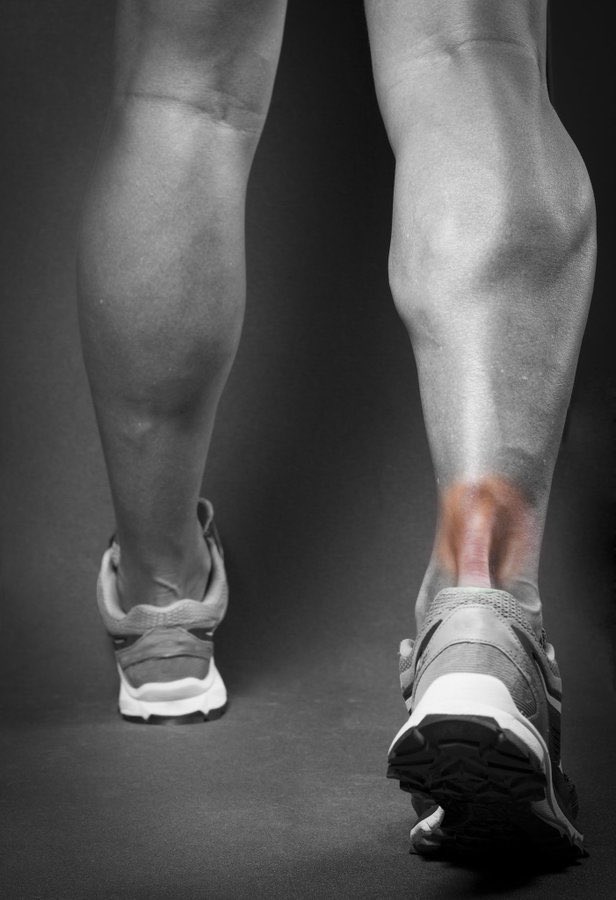

يحدث التهاب او تمزق #الوتر_العرقوبي

♦️الاستخدام المفرط لوتر العرقوب

♦️في العدائين الرياضين نتيجة التحميل الزائد

♦️لدى الأشخاص الذين يمارسون الرياضية فقط في عطلة نهاية الأسبوع

♦️#السمنة و تفلطح القدم تزيد من الخطورة

♦️بعض الادوية مثل الفلوروكينولونات

أعراض التهاب #الوتر_العرقوبي

🔻يبدأ الألم المصاحب على هيئة وجع خفيف في الجانب الخلفي للساق أو أعلى الكعب بعد ممارسة النشاط الرياضي

🔻قد تحدث نوبات ينتج عنها الشعور بألم أكثر شدة بعد الجري أو صعود السلالم

🔻وجع أو تيبس خاصة في الصباح، والذي عادة ما يتحسن مع اليوم بعد الحركة